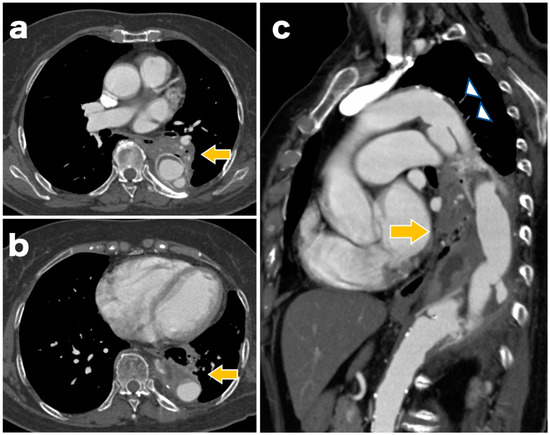

The surgery was performed under general anesthesia. First, a 26 × 26 × 200 mm stent graft (GORE® TAG® Conformable Thoracic Stent Graft with ACTIVE CONTROL System, W.L. Gore and Associates, Flagstaff, AZ, USA) was inserted at the distal site via the left common femoral artery. Subsequently, a 28 × 28 × 150 mm stent graft was inserted at the proximal site, and the region from Zone 3 was implanted at the level of the 12th thoracic vertebra (Figure 3). The final aortograph showed a slight type 1a endoleak, but ballooning was not performed because of the known dissection findings on the proximal side.

Figure 3. Postoperative contrast-enhanced computed tomographs showing no migration or fracture of the stent graft and no obvious endoleak.